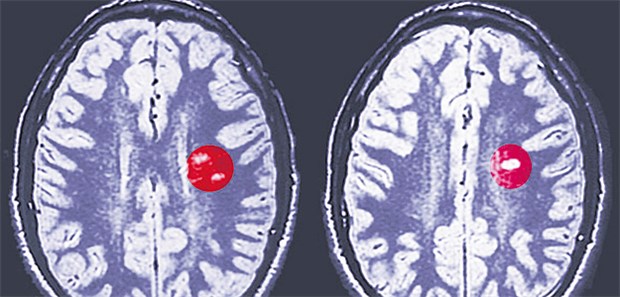

MRT-Aufnahme des Gehirns bei einem Patienten mit Multipler Sklerose. Die Herde sind umrandet.

© Arteria Photography

Phase-II-Studie

Statin bremst sekundär progressive MS